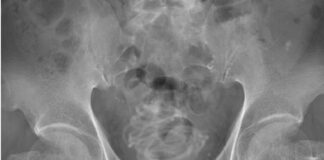

Olay Japonya’da meydana geldi. Ağrılar içinde hastaneye kaldırılan ismi açıklanmayan adam kasıklarında...